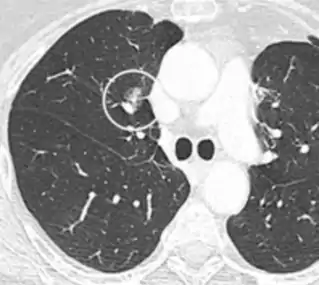

Round well-delineated solid lung nodule with smooth border.[9]